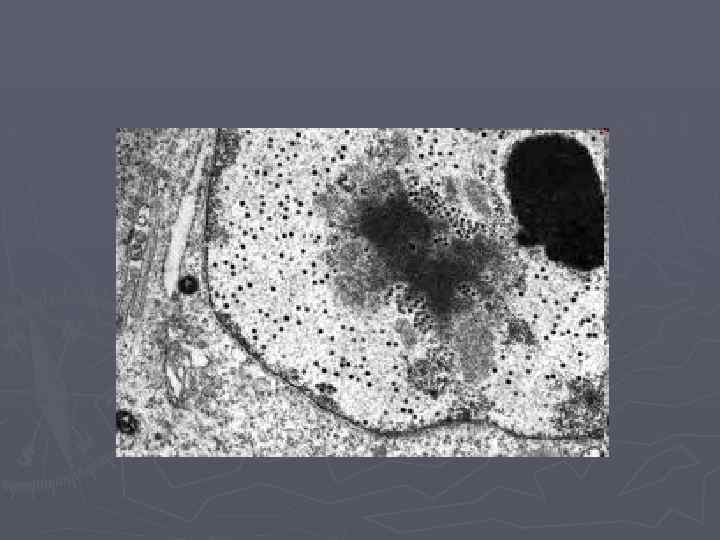

Электрондық микроскоппен қарағанда бұл тамшылардың өте ірі, ыдырап жатқан лизосомалар екені анықталған. Бұл өзгерістер негізінен бүйрек өзекшелерінің эпителиінде, бүйрек шұмақтары сүзгісінің өткізгіштігінің күшейгенде немесе белоктардың бүйрек өзекшелерінде қайта сорылу бұзылғанда көрінеді. Сонымен гиалин тамшылы дистрофия гломерулонефритке байланысты дамыған нефроздық синдромда, бүйрек амилоидозында, диабетте айқын көрінеді. Бүйректің сыртқы көрінісі осы дистрофияның қай науқасқа орай шыққанына байланысты.

Гиалинді – тамшылы дистрофия дамығанда цитоплазмада бір-бірімен бірігіп, клетканың цитоплазмасын толтырған, гиалинге ұқсас ірі белок тамшылары пайда болады да, клетканың ультрақұрылымдық элементтері қирайды. ► Бірқатар жағдайларда гиалинді-тамшылы дистрофия фокальды (латынша: focus - ошақ) коагуляциялық (латынша: coagulatio - ұйыту) некрозбен аяқталады. ► Диспротеиноздың бұл түрі бүйректерде жиі кездеседі де, бауырда сирек, ал миокардта өте сирек байқалады. ► Бүйректі микроскоппен зерттегенде оның нефроциттерінен гиалин тамшылары табылады. ► ►